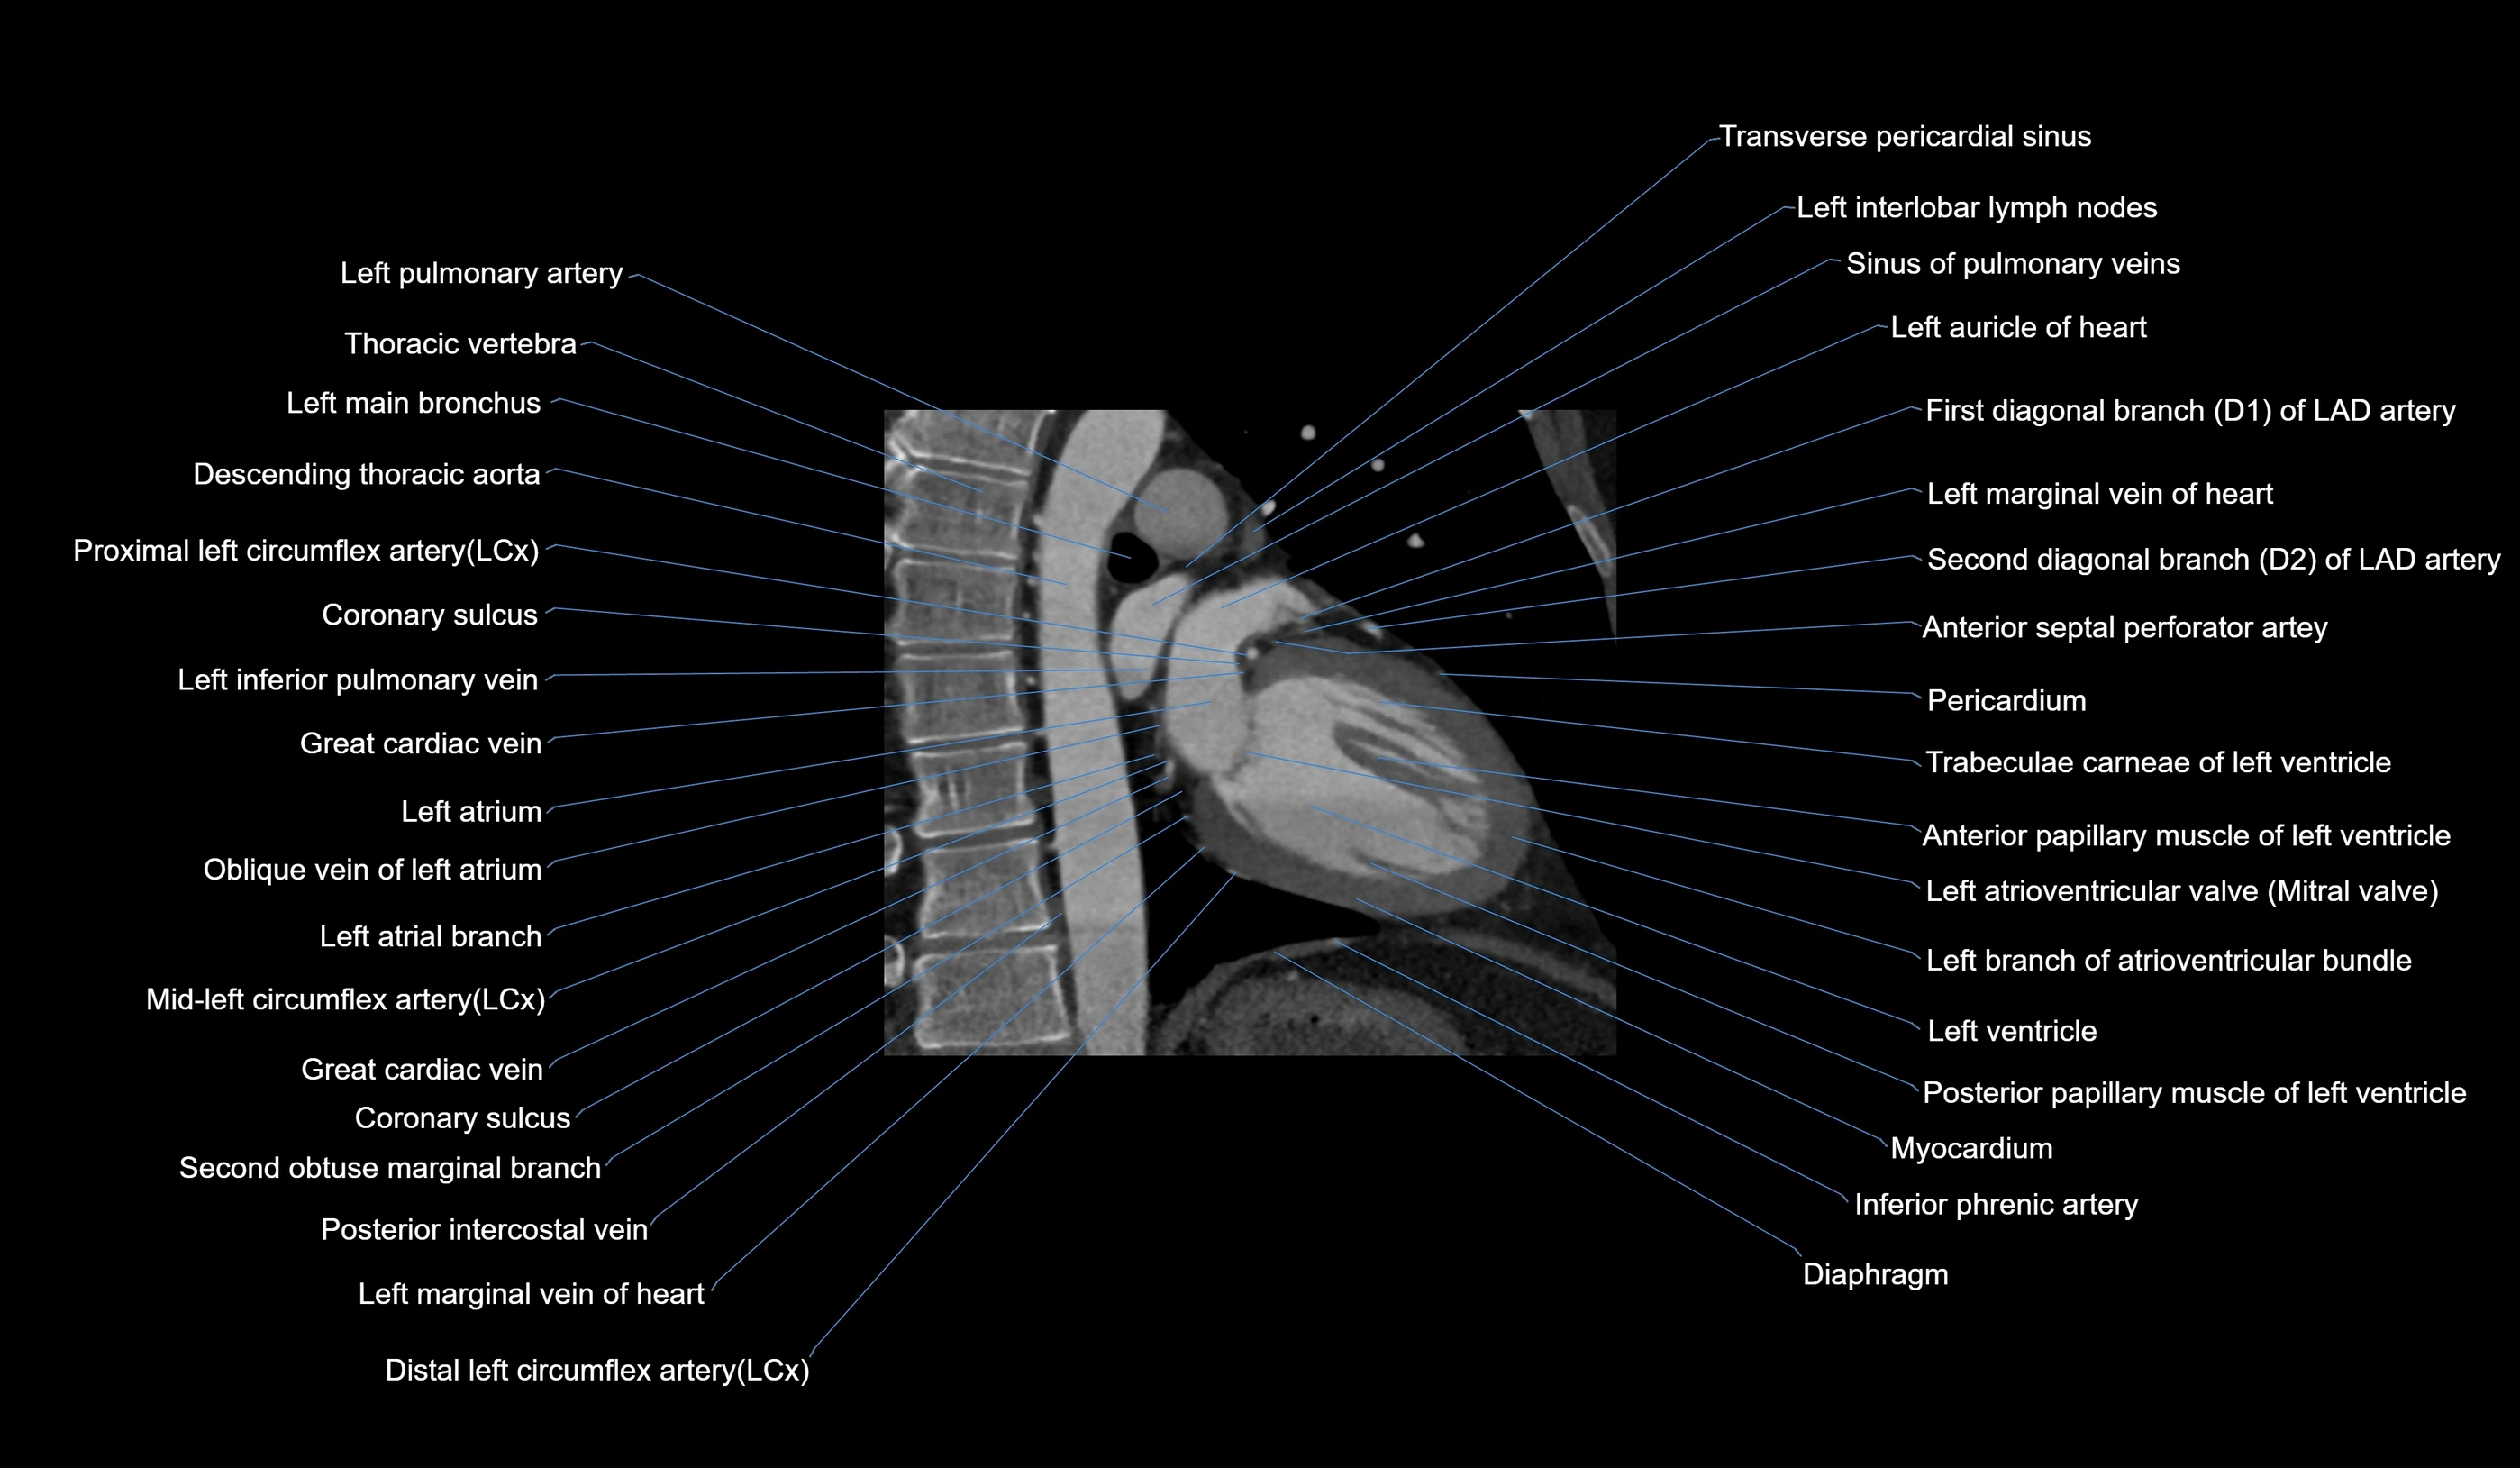

CT images